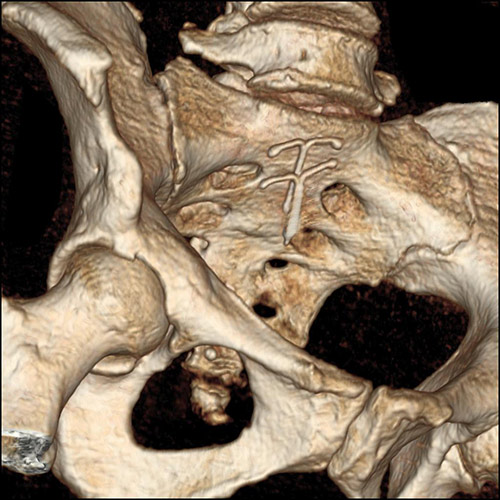

En kvinne i slutten av 40-årene ble innlagt på kirurgisk avdeling grunnet magesmerter. Standard CT-undersøkelse av abdomen/bekken viste ingen årsak til pasientens smerter, men som bifunn ble det påvist to spiraler i uterinkaviteten, her presentert som 3D-rekonstruksjon (bildet til venstre) og tykk multiplanrekonstruksjon (bildet til høyre) av CT-opptaket. Ved søk på PubMed finner vi bare ett liknende rapportert tilfelle av to spiraler i uterus (1).